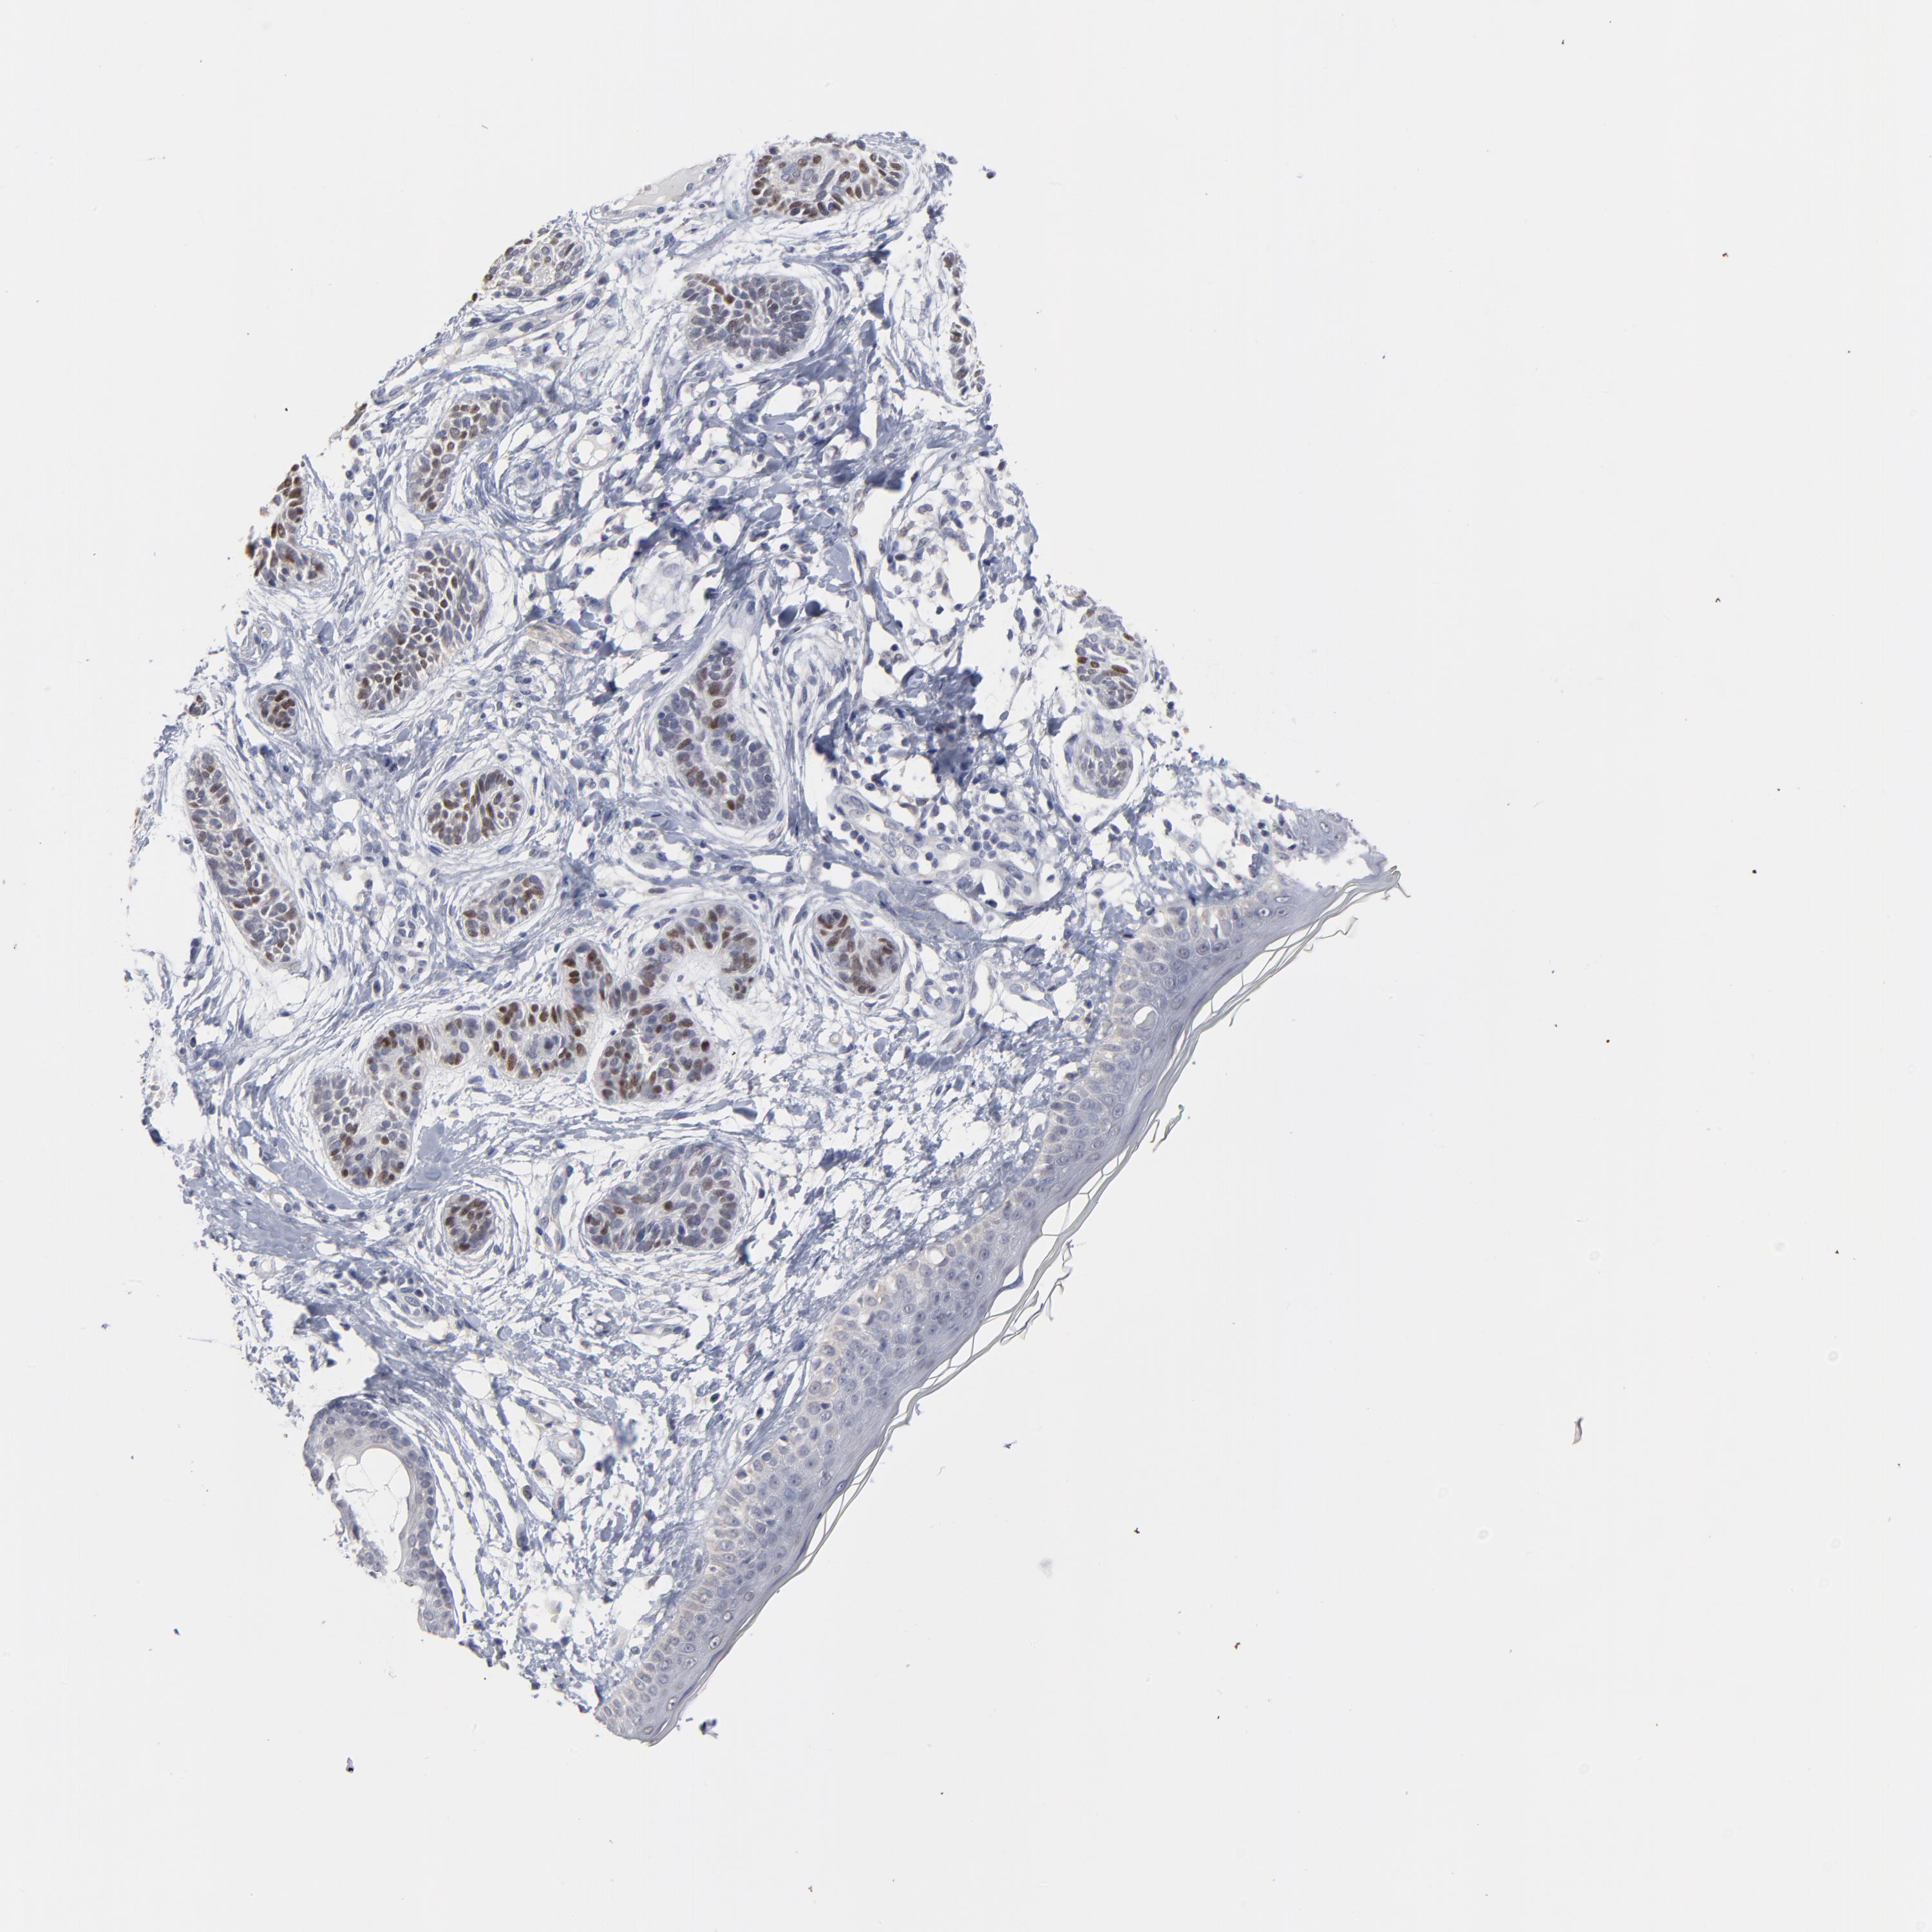

SKIN CANCER - Protein expressioni

A mouse-over function shows sample information and annotation data. Click on an image to view it in a full screen mode. Samples can be filtered based on level of antibody staining by selecting one or several of the following categories: high, medium, low and not detected. The assay and annotation is described here.

Antibody stainingi

Antibody staining in the annotated cell types in the current human tissue is reported as not detected, low, medium, or high, based on conventional immunohistochemistry profiling in selected tissues. This score is based on the combination of the staining intensity and fraction of stained cells.

Each image is clickable and will lead to virtual microscopy that enables deeper exploration of all samples and also displays staining intensity scores, fraction scores and subcellular localization as well as patient and tissue information for each sample.

Antibody HPA003333

Staining

High

Medium

Low

Not detected

Intensity

Strong

Moderate

Weak

Negative

Quantity

>75%

75%-25%

<25%

None

Location

Nuclear

Cytoplasmic/membranous

Cytoplasmic/membranous,nuclear

Squamous cell carcinoma, NOS

Basal cell carcinoma